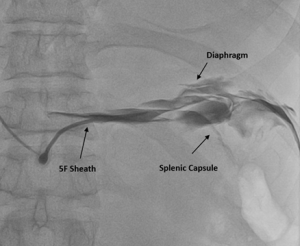

Fluoroscopy was done, and the sheath was found to be in the splenic capsule (Figure 1). Under fluoroscopic guidance, a pigtail was inserted over a 0.035” J-tipped Terumo wire, after confirming the position of the wire in the pericardial space (Figure 2), and 250 ml of pericardial fluid was drained. Post-pericardiocentesis, the patient was vitally stable.